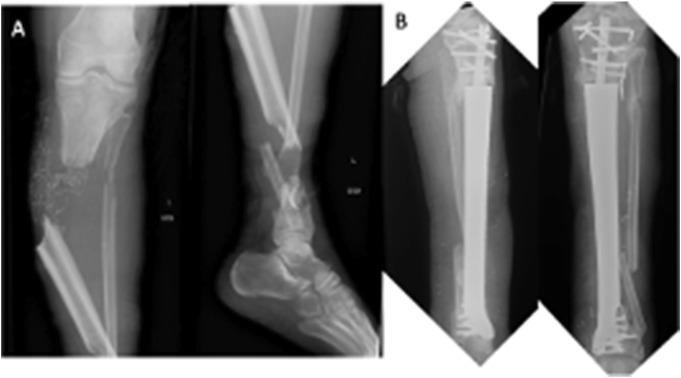

2023年骨科创伤协会的基础科学焦点论坛举办了一场关于骨科增材制造(AM)的研讨会。三位专家介绍了增材制造的各个方面:Malcolm DeBaun博士讨论了用于节段性骨质流失的定制3D打印植入物,Samir Mehta博士探讨了3D打印在教育和手术计划中的应用,Guha Manogharan博士阐述了增材制造和混合制造中的挑战和机遇。研讨会强调了增材制造在骨科创伤的临床、教育和工业应用中的重大影响。

The 2023 Orthopaedic Trauma Association's Basic Science Focus Forum featured a symposium on additive manufacturing (AM) in orthopaedics. Three experts presented on various aspects of AM: Dr. Malcolm DeBaun discussed custom 3D-printed implants for segmental bone loss, Dr. Samir Mehta explored 3D printing in education and surgical planning, and Dr. Guha Manogharan addressed challenges and opportunities in AM and hybrid manufacturing. The symposium highlighted AM's significant impact across clinical, educational, and industrial applications in orthopaedic trauma.